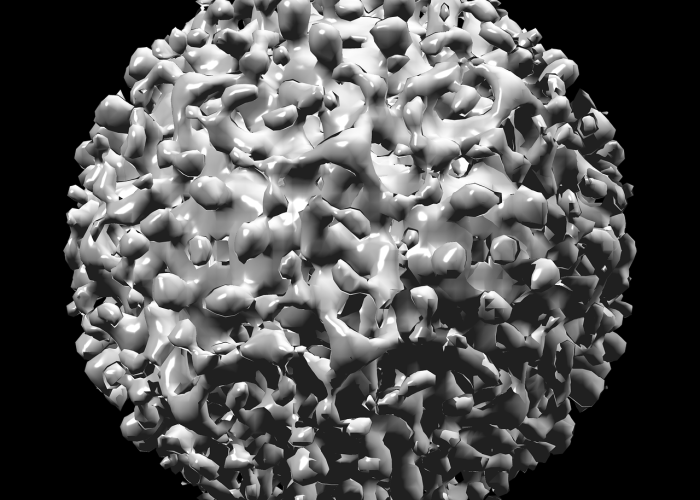

主要流行毒株的演变 疫情初期,非洲主要输入并流行原始毒株及早期变异株,随着全球疫情发展,具有高传染性的贝塔(Beta)变异株(B.1.351)和德尔塔(Delta)变异株(B.1.617.2)相继在非洲多地成为主导毒株,导致感染人数激增,医疗系统承压,2021年底以来,传播力更强的奥密克戎(Omicron)变异株及其亚型(如BA.1、BA.2、BA.4、BA.5等)逐渐取代其他毒株,成为非洲主要流行株,奥密克戎的强免疫逃逸能力导致多轮疫情高峰,但其引发的重症率相对较低,部分原因可能与非洲年轻人口结构和既往暴露产生的免疫背景有关。

非洲疫情中的病毒毒株演变是全球疫情动态的重要组成部分,从贝塔、德尔塔到奥密克戎,每一次毒株更替都影响着非洲的疫情轨迹,持续加强病毒监测、促进疫苗公平、并关注非洲特殊的流行病学背景,将是应对新毒株挑战、保障全球公共卫生安全的关键。